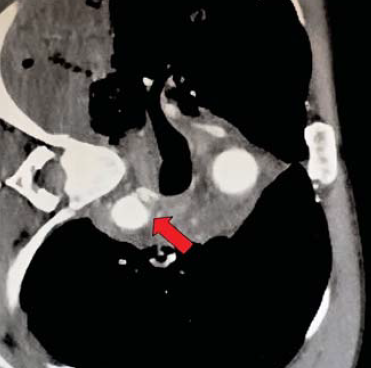

9. ábra.

Kerékpárját toló beteg autógázolás áldozataként sérült. Agyrázkódást szenvedett. Lumbalis gerincsérülését, lábszártörését és az aorta descendens tompa sérülését CTA igazolta.

9. 40 éves férfit kerékpárosként autó gázolt el. Eszméletlen állapotban, intubálva, jobb lábszártöréssel, háti és lábszári lágyrész sérülésekkel került felvételre. CT vizsgálattal koponyaűri vérzés kizárható volt, mindkét pleura űrben jelentős folyadékmennyiséget, máj, vese és jobb tüdő contusiót, proximalis aorta descendens traumás dissectioját, valamint a Th XI-XII szinten discoligamentaris instabil gerincsérülést és következményes gerincvelő contusiót igazoltunk (9. ábra).

Neurológiai vizsgálattal petyhüdt alsó végtagi paraplegia volt kimutatható. Tudata visszatért. 24 órán belül, keringési paramétereinek stabilizálása után, stent graft implantatiot, majd másnap ThX-LII segmentumban transpedicularis gerincrögzítést végeztünk (10.,11., 12. ábra). Paraplegia mellett lábszártörését egy héttel később lemezes osteosynthesissel oldottuk meg. A postoperativ szakban septicus szövődmények alakultak ki mind lágyrész sérüléseinek mind gerincműtétének területén. Hosszas antibiotikus kezelés mellett septicus állapota rendeződött. Parapareticus állapotban került vissza a beküldő kórházba rehabilitatio céljából. A betegek és ellátásuk adatainak összefoglalását I, II és III táblázat mutatja.